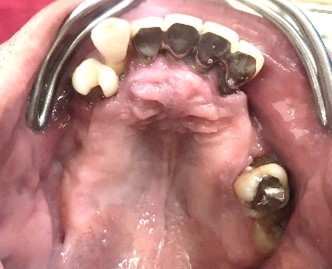

【義歯を外したところ】